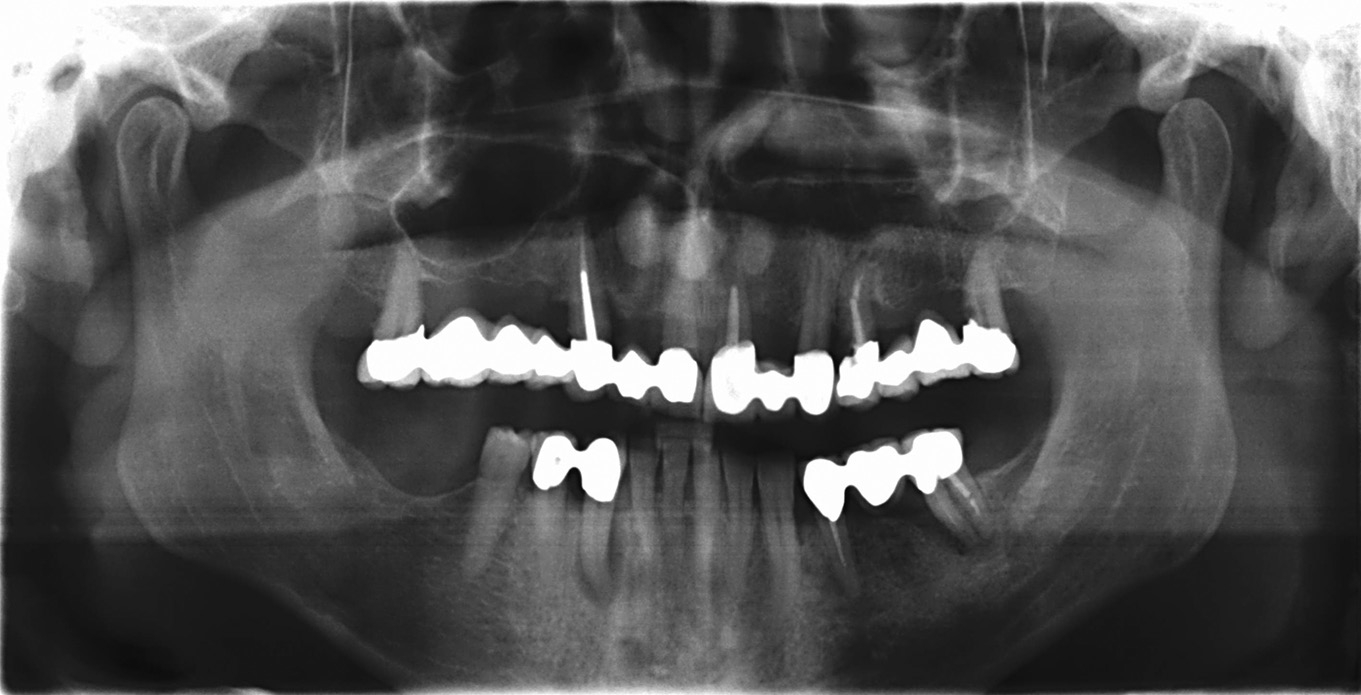

Zur implantatgetragenen prothetischen Versorgung zahnloser Patienten stehen dem Behandlungsteam verschiedene Konzepte zur Verfügung. Die Bemühungen nach möglichst einfachen Behandlungsmethoden führten in den vergangenen Jahren zur Modifikation klassischer Protokolle. So kann beispielsweise mit dem Konzept der Sofortversorgung die Behandlungszeit signifikant reduziert werden. Die Arbeitsgruppe um Prof. Dr. P. Maló hat das Konzept der schräg in den Kiefer inserierten Implantate zur festsitzenden Therapie des zahnlosen Ober- und Unterkiefers – unter Vermeidung von Sinusbodenelevation und Nervlateralisation – etabliert [3-5]. Die Untersuchungen der Arbeitsgruppe zeigen eine kumulative Überlebensrate von 97,6 Prozent [8]. Grundsätzlich erfordert das in seinem Aufwand reduzierte Therapiekonzept eine exakte präoperative Diagnostik sowie abgestimmte, für die Indikation konzipierte Implantatbauteile [1,6,7]. Ein seit Jahren bewährtes System basierend auf dem Protokoll ist SKY fast & fixed (bredent medical, Senden). Zusätzlich zur Möglichkeit der sofortigen temporären Versorgung liegen die Vorteile in der flexiblen Umsetzung der finalen Restauration. Aufgrund der hohen Patientenakzeptanz der temporären Brücke wird bis zur Herstellung der definitiven Versorgung ein großes Zeitfenster geboten, in welchem u. a. die Patientenbedürfnisse evaluiert werden können. In der Regel kann nach drei bis vier Monaten mit der Umsetzung der definitiven Versorgung begonnen werden [1].

Unter anderem beruht die Akzeptanz des Konzeptes darauf, den vorhandenen Knochen bestmöglich zu nutzen und knochenaufbauende Maßnahmen weitestgehend zu minimieren. Dadurch können sich jedoch unter Umständen ungünstige Implantataustrittstellen ergeben, was bei der Gestaltung der Suprakonstruktion limitierend ist, z.B. wenn der Schraubenkanal im sichtbaren Bereich platziert werden müsste. Um in diesen Situationen entsprechend Spielraum für die ästhetische Gestaltung zu schaffen, kann die transversale Verschraubung (Verbolzung) des Zahnersatzes mit den Implantaten eine adäquate Möglichkeit sein. Hierfür werden Prothetikkappen angeboten (bredent medical), die eine transversale Verschraubung – selbstzentrierende Transversalverschraubung – ermöglichen. Die Schraubenkanäle werden in den nicht sichtbaren Bereich positioniert. Die industriell vorgefertigten Bauteile vereinfachen die Arbeit und stellen eine hohe Präzision sicher. Das Vorgehen wird anhand eines Patientenfalles beschrieben. Es wird gezeigt, dass mit der transversalen Verschraubung selbst schwierige Ausgangsverhältnisse sicher und zuverlässig gelöst werden können.

Der Patient konsultierte während der kommenden Wochen regelmäßig die Praxis. Der postoperative Verlauf gestaltete sich problemlos. Nach vier Monaten zeigten sich osseointegrierte Implantate sowie stabile Hart- und Weichgewebeverhältnisse. Für die Herstellung der definitiven Brücke sind unterschiedliche Konzepte möglich. In diesem Fall sollte eine verschraubte Versorgung gefertigt, das Gerüst mit Komposit verblendet sowie die Restauration farblich individualisiert werden. Da schon bei der Herstellung der temporären Brücke festgestellt worden ist, dass die okklusale Verschraubung aufgrund der sichtbaren Schraubenkanäle zu ästhetischen Problemen führt, war eine transversale Verschraubung (Verbolzung) des Zahnersatzes auf den Implantaten angedacht.